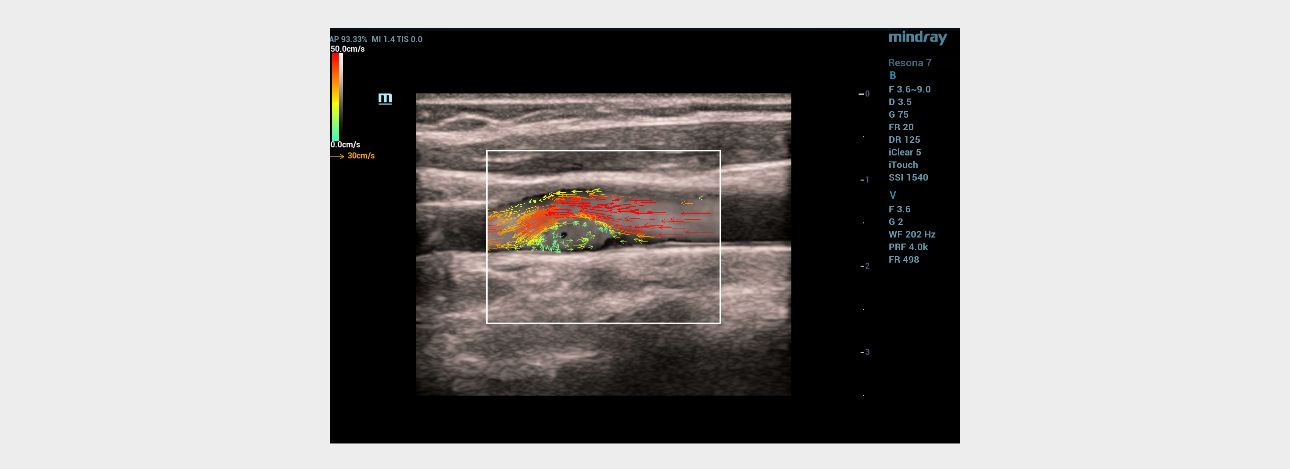

Ultrasound examination ŌĆō vector analysis of blood flow mode (V Flow)

When the vector analysis mode (V Flow) was activated, the complete filling of the lumen of the left common carotid artery in the bifurcation area with colored vector arrows was clearly traced. The following changes were registered immediately after the linear hyperechoic structure: 1) shorter color arrows compared to arrows from the main blood flow in the vessel; 2) the arrows had a different color pattern (green, blue, yellow) in contrast to the red and orange arrows of the main stream; 3) the short arrows had a multidirectional, vortex-like direction in contrast to the laminar flow, which was determined over the pathological area of the vessel with a hyperechoic linear structure (Fig. 4). Given the absence of signs of flotation of hyperechoic linear formations and the topical symmetry of the location, it was assumed that these changes are characteristic of the carotid web.

Ultrasound vector analysis of blood flow

The V Flow mode made it possible to clearly see the full filling of the vessel lumen with colored arrows directly behind the hyperechoic linear formation on the left. The direction, color and size of the arrows in this area of interest clearly provided information about the slow-speed, retrograde and then vortex-like flow of blood in the vessel, which explained the poor color filling of the vessel lumen directly behind the hyperechoic linear structure in the color Doppler mapping mode, due to the high dependence of the latter on the speed and direction of moving blood particles (erythrocytes). The technology of vector analysis of blood flow made it possible to exclude the presence of an atherosclerotic plaque or a parietal thrombus.